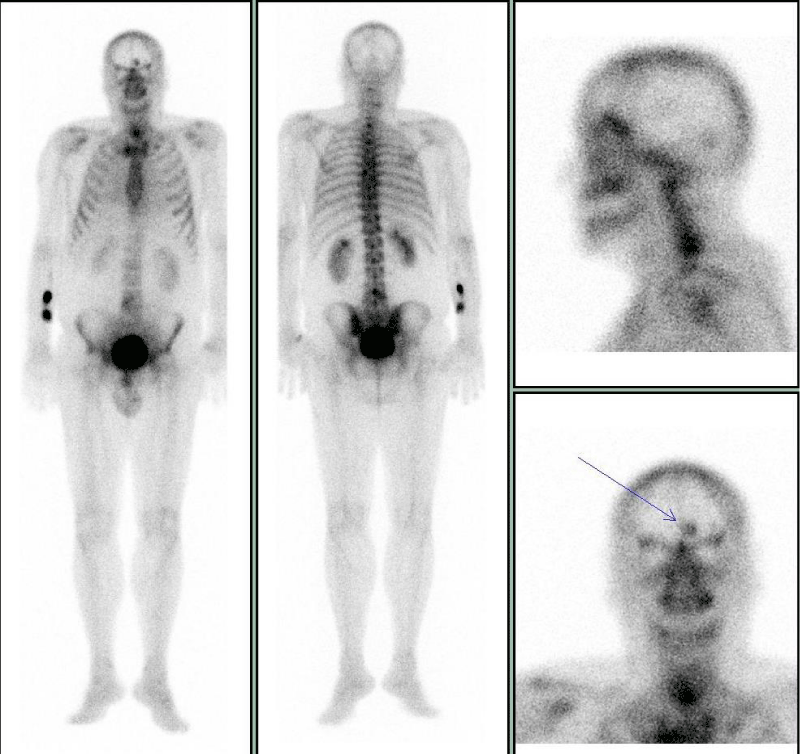

Case 3: Meningioma on 99mTc-HDP bone scan

A 62-aged man referred to 99mTc-byphosphonates bone scintigraphy for the staging of recent diagnosed lung cancer. Concerning the main clinical request, the bone scan whole body image, obtained 2 hours after the i.v. injection of the osteotropic radiopharmaceutical, did not show any pathologic uptake of the tracer in the skeleton, excluding an uptake in L4 vertebrae, potentially due to osteodegeneration. Conversely, focusing on the head region, it was evident a focal area of increased uptake in para-median left frontal area (Figure 3). The man had no previous significant neurologic symptoms in recent anamnesis. Both the locus of this uptake (frontal bone or soft tissues) and the cause of this uptake were unclear, therefore we suggested to perform a complementary morpho-structural examination. The CT scan subsequently performed reported a great meningioma localized in left frontal area, with Calcium deposits included (Figure 4).